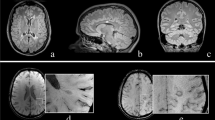

In contrast to microbleeds, the phenomenon described in our current study occurs strictly within otherwise T2w/Fluid attenuated inversion recovery (FLAIR) hyperintense lesions. Furthermore, by definition, microbleeds can reach a size of up to 10 mm. However, the changes we describe, are limited to a small spot. In this respect, we consider the changes in SuS to be morphologically different from microbleeds. Brain lesions in MS can also show paramagnetic signal changes in the center of rather new lesions as a result of demyelination or smaller iron deposits released by dying iron-rich oligodendrocytes. In this case, SWI hypointense signals are more diffusely distributed and occupy a larger proportion of the lesion, whereas we see a concentration of signal toward a small spot in Susac lesions. Also, “iron rims” can be observed around MS lesions as a potential imaging marker of iron-laden CD68 positive cells and chronic inflammation [20,21,22]. In the event of very small MS lesions, it is conceivable that similar appearances to those seen in SuS could occur. In this case, the distribution and localization of the lesions could help to differentiate between the two conditions. For differentiation between the “iron dot” sign in SuS and CVS and T2*w hypointense core lesions in MS see Fig. 3.

Comparison of lesion morphology of “iron dot” lesions in Susac syndrome (bottom) and multiple sclerosis (top). The figure illustrates differences in morphology on 7T T2*w images between “iron dots” in Susac syndrome (red arrows) and the central vein sign (white and black arrow) as well as T2*w hypointense core lesions (blue arrows with zoom) in multiple sclerosis (MS). All exemplary T2*w images in the bottom are from different Susac patients. Please note that the “iron dots” in Susac syndrome (red arrows) appear punctate and sharply delineated on T2*w. Contrarily, the T2*w hypointense core lesions (blue arrows with zoom) in MS often appear just slightly less hyperintense on T2*w in comparison to other MS lesions. Only when the lesion is viewed on strongly susceptibility weighted sequences (right) does a rather diffuse signal loss become apparent. The central vein sign in MS also appears as a point-like, pronounced hypointensity on T2*w images when the slice plane is perpendicular to the long axis of the MS lesion (white arrow). However, if the slice plane is parallel to the long axis of the lesion, the CVS can be recognized as a straight line running through the center of MS lesions (black arrow)